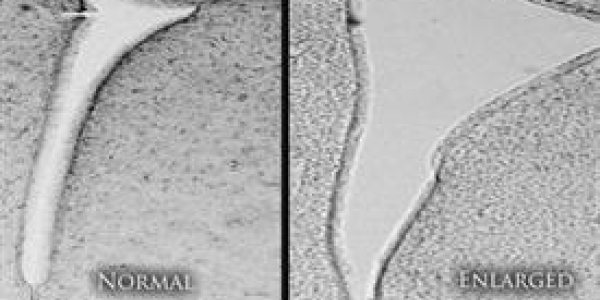

A recent paper found that exposure to air pollution early in life produces harmful changes in the brains of mice, including an enlargement of part of the brain that is seen in humans who have autism…